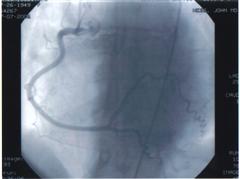

Heart 3 Heart 4